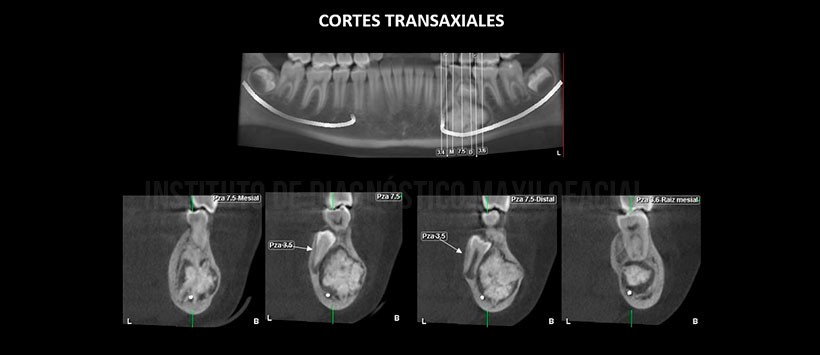

A la evaluación de la tomografía volumétrica (CBCT) en cortes axiales (Figura 2), coronales (Figura 3), transaxiales (Figura 4) y tangenciales (Figura 5) se aprecia múltiples imágenes hiperdensas de diferentes formas y tamaños con aspecto a piezas dentarias (denticulos), delimitado por un halo hipodenso localizado en cuerpo mandibular izquierdo que se extiende en sentido mesio-distal de raíz mesial de pieza 36 a zona apical de pieza 35, en sentido cefálico-caudal del reborde basal mandibular hasta zona próxima a la cresta alveolar. Así mismo se observa desplazamiento caudal del conducto dentario inferior, adelgazamiento y desplazamiento de la tabla ósea vestibular e impactación de la pieza 35 la misma que se encuentra en posición vertical a nivel de la tabla ósea lingual y persistencia de pieza 75.